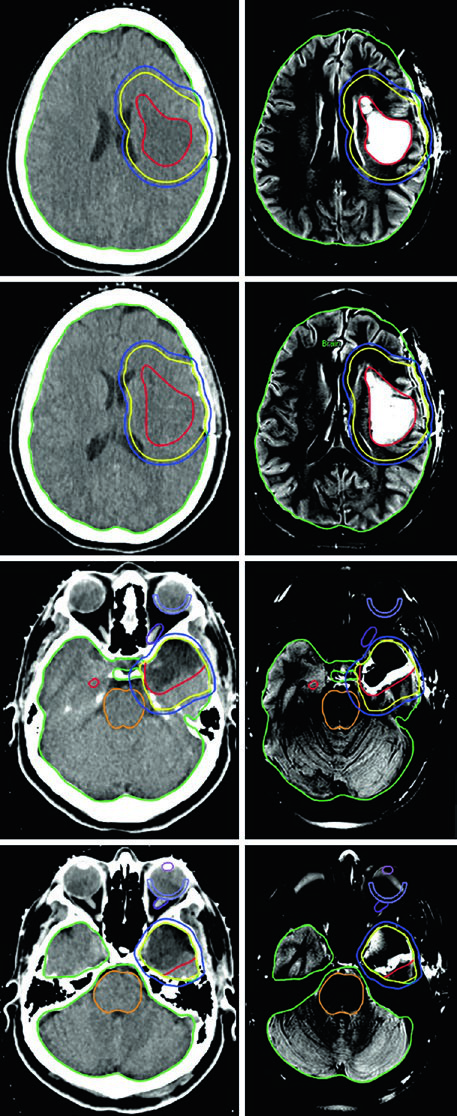

Un punto práctico fundamental: la evaluación por TC es esencial para decidir si los cambios periósticos y óseos deben incluirse en el GTV. En el ejemplo del meningioma del seno cavernoso (Figura 29.7), el tumor fue delineado con RM de planificación, recibió margen de 2 mm para el PTV y fue tratado a 52,2 Gy en 29 fracciones. Las líneas de isodosis muestran conformación estrecha alrededor del tronco encefálico, quiasma, nervios craneales adyacentes, arteria carótida y cóclea derecha.

Los meningiomas selares y supraselares voluminosos con resección incompleta — como en la Figura 29.8 — pueden requerir expansión de PTV de 3 mm debido a la enfermedad residual extensa. La relación íntima con ambos globos oculares y el tronco encefálico exige una planificación dosimétrica cuidadosa, frecuentemente con IMRT o VMAT para conformar la dosis y proteger estas estructuras críticas.